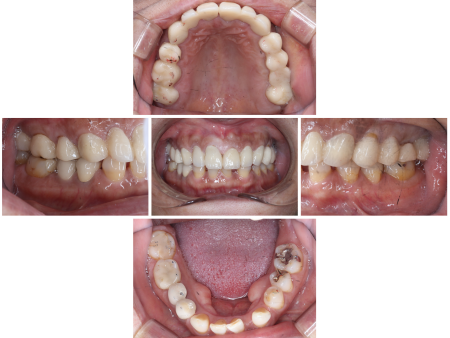

「上の前歯が痛い」とご相談いただきました。

拝見したところ、右上前歯2本(中切歯/1番、側切歯/2番)の根の周りに炎症が認められ、痛みの原因になっていました。

しかし今回の患者様の場合、前歯のすり減りが激しく噛み合わせが低くなっていたため、このままの状態で治療を進めると被せ物を装着した歯が下の前歯に強く当たり過ぎて、被せ物や土台、歯の根も割れてしまう恐れがあります。

また、全体的に歯の着色も見られ、詳しく調べてみたところ、歯の形成期にテトラサイクリン系の抗生物質を大量に服用したことが原因で歯が変色してしまう「テトラサイクリン歯」であることもわかりました。

根の炎症を改善するために右上前歯2本の根管治療を行ったあと、上の歯すべて(右の第2大臼歯/7番〜左の第2大臼歯)に強度のある被せ物を装着する治療を提案しました。

右上前歯2本だけでなく、上の歯全体に新たな被せ物を入れることで、噛み合わせが全体的に上がり被せ物や歯の根が割れるリスクを回避できます。また、白くそろった歯の色に仕上がることもお伝えしたところ、同意いただきました。